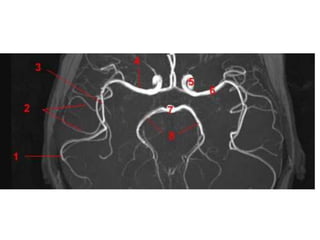

Arteries of the brain (cranial view) - MRA

1. Anterior cerebral artery

2. Anterior communicating artery

3. Basilar artery

4. branches (in insula) of middle

cerebral artery

5. Cavernous portion of internal carotid

artery

6. Cervical portion of internal carotid

7. Genu of middle cerebral artery

8. Intracranial (supraclinoid) internal

carotid artery

9. Middle cerebral artery

10. Ophthalmic artery

11. Petrous portion of internal carotid

12. Posterior cerebral artery

13. Posterior cerebral artery in ambient

cistern

14. posterior cerebral artery in

interpeduncular cistern

15. Posterior communicating artery

16. Posterior inf cerebellar artery.

17. Quadrigeminal portion of posterior

18. Superior cerebellar artery

19. Vertebral artery